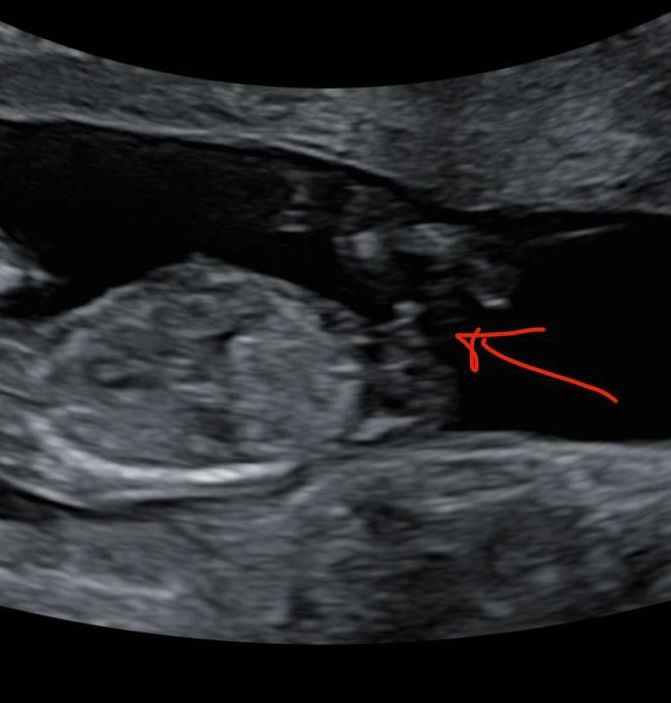

И вот 6 недель ровно я приезжаю эмбрион на месте сб + , но мне говорят что место мой мальчик выбрал неудачное… что возможно это вб, эмбрион прикрепился в на выходе из трубы, в этом месте где вроде бы уже матка, но ткани трубные и при росте пя матка может просто порваться и в итоге кровоизлияние с очень большим процентом летальных исходов. Врач сказала что меня отправляют на экспертное узи , если врач подтверждает , то делают чистку, так как моя жизнь в приоритете. Вы не представляете сколько слез было пролито …

Через два дня новое узи, гробовая тишина и вердикт «я склонен предполагать все же, что у вас маточная беременность, но надо следить» самое тонкое место миометрия у меня составляло 3,5мм, а дальше начались еженедельные узи , на которые я шла с замерением сердца, миометрий так и оставлялся 3.5 пя расположилось в правом рогу и занимало там все место ) я наблюдала как моя коеветочка растёт, но были очень страшно и за себя и за Малыша, не буду скрывать, но плакала я часто. за это время я прочитала все публикации зарубежных врачей на тему угловой беременности и понимала , что тут баш на баш, сомнения были только из-за меометрия , который по исследованиям должен был быть минимум 5мм. Так мы дожили до первого скрининга, на котором нам сказали что 95% прогноз что все будет хорошо, и первое предположение что у нас будет сын ))